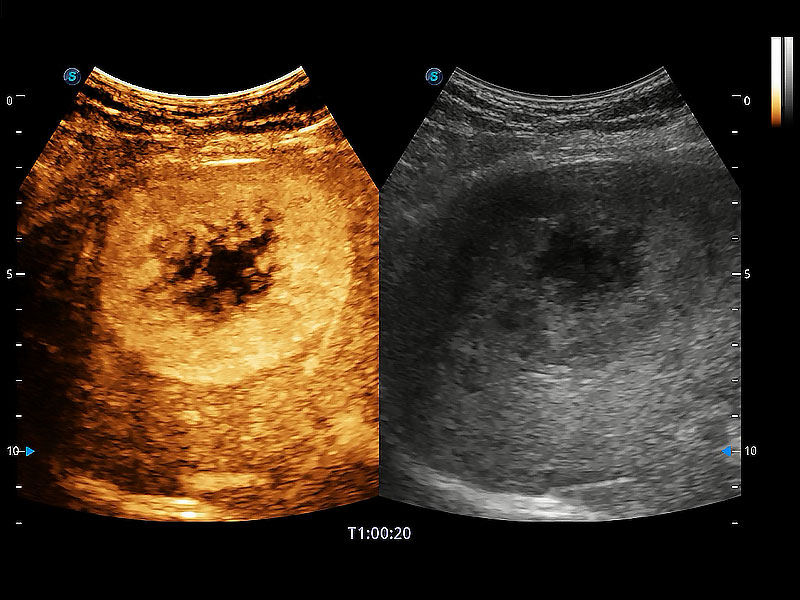

非線性融合造影成像充分利用諧波和基波信號(hào),為難以觀察的血流進(jìn)行增強(qiáng)顯像。可用于線陣、凸陣、微凸陣、相控陣探頭。